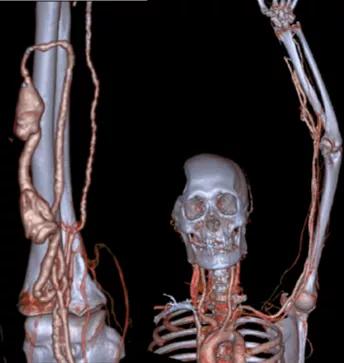

张东亮主任耐心听完患者的叙述,给出了诊断: “肿胀手综合征” 。肿胀手的主要原因是自体动静脉内瘘成型后,静脉发生动脉样改变,管腔内静水压力升高,当静脉血液回流不畅时就会导致压力进一步升高,从而形成患侧手臂显著增粗的病症,这在起搏器植入的血透患者中,发生率更高。张主任立刻为老李安排检查:首先是超声明确内瘘吻合口内径,发现血管流量尚可,静脉弓汇入锁骨下静脉处相对性狭窄伴迂曲。随后又进行了上肢及深静脉CT三维重建(CTA+CTV),发现主要病变为锁骨下静脉汇入头臂静脉处静脉瓣增生狭窄(如下图)

病变明确了,张主任当机立断,立即进行介入手术。张东亮主任医师与付晨主治医师在新建成的新龙泽院区介入手术中心进行了局麻下经皮穿刺血管内介入治疗。张主任凭借丰富的经验、娴熟的手法很快将超滑导丝通过病变部位,10mm高压球囊将狭窄部位扩张至无回弹,再次造影确认,心细的张主任又发现了新的端倪——近心端静脉还有一处狭窄!此前这一病变在CTA+CTV结果中并没有发现,张主任毫不犹豫,球囊再前进50mm、*压打**扩张,再次造影复测,血流通畅、侧支循环和返流消失。